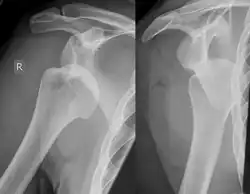

Diagnosis can be suspected by history and physical examination which is usually followed by imaging. Because of the mechanism of injury, apprehension of anterior dislocation is common with provocative maneuvers. Hill–Sachs lesions have been classified as "engaging" or "non-engaging", with engaging lesions defined by the ability of the glenoid to sublux into the humeral head defect during abduction and external rotation. Engaging dislocations have a higher risk of recurrent anterior dislocation, and their presence can help guide surgical management.[2] Imaging diagnosis conventionally begins with plain film radiography. Generally, anteroposterior (AP) radiographs of the shoulder with the arm in internal rotation offer the best yield while axillary views and AP radiographs with external rotation tend to obscure the defect. However, pain and tenderness in the injured joint make appropriate positioning difficult and in a recent study of plain film x-ray for Hill–Sachs lesions, the sensitivity was only about 20%. i.e. the finding was not visible on plain film x-ray about 80% of the time.[3]

The incidence of Hill–Sachs lesion is not known with certainty. It has been reported to be present in 40% to 90% of patients presenting with anterior shoulder instability, that is subluxation or dislocation.[8][9] In those who have recurrent events, it may be as high as 100%.[10] Its presence is a specific sign of dislocation and can thus be used as an indicator that dislocation has occurred even if the joint has regained its normal alignment. Large, engaging Hill-Sachs fractures can contribute to shoulder instability and will often cause painful clicking, catching, or popping. The average depth of Hill–Sachs lesion has been reported as 4.1 mm.[11]